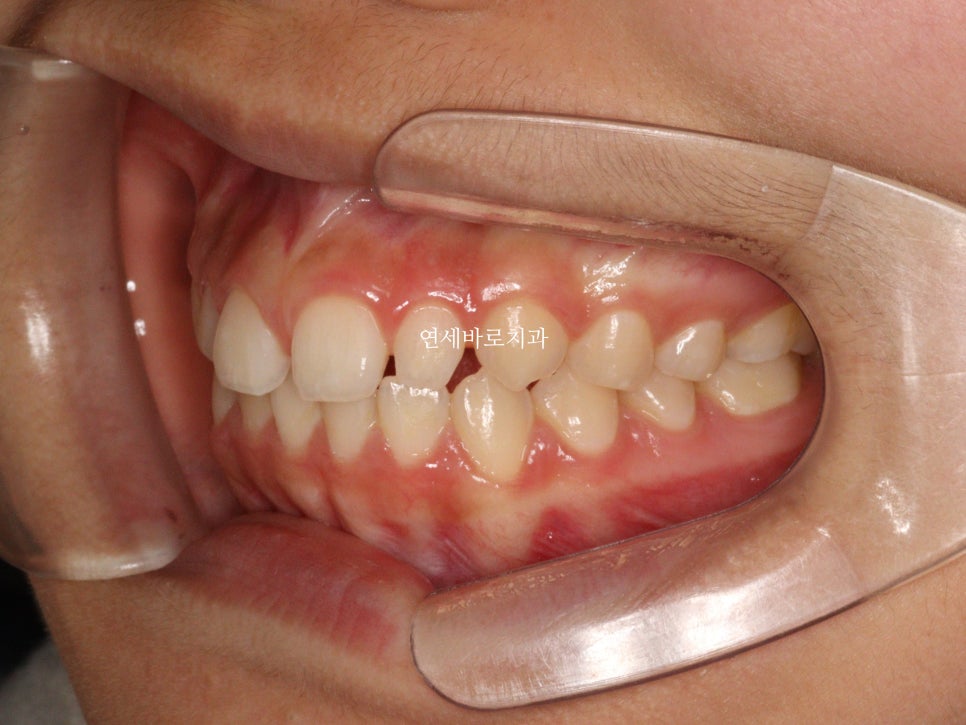

앞니가 벌어져있고

왜소치가 있는 아이였습니다.

치아의 형태도 이상적인 형태와는 좀 달라서

1월에 왔던 아이입니다. 어금니 교합은 너무나 좋아서 건들일것이 없었어요

앞니만 부분교정으로도 충분했습니다.